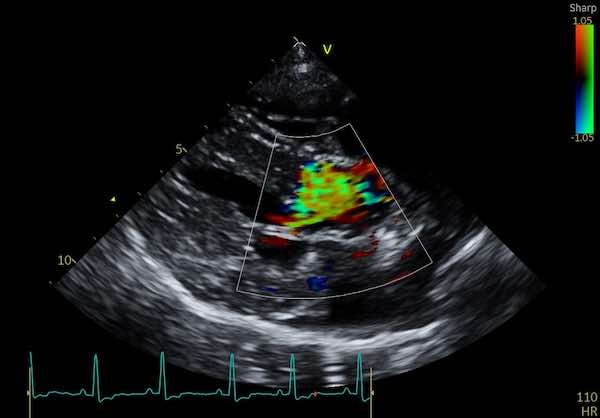

The cause is typically turbulent blood flow in the heart. Imagine a fast-moving river that flows quietly until it reaches a constriction, such as a bridge or rapids. That constriction causes the water to become noisy and chaotic. The same principle applies to blood flow inside your dog’s heart. When blood flow becomes turbulent due to an issue like a leaky valve or narrowing of a vessel, it creates sound waves that we hear as a murmur.

Image: Turbulent flow on colour doppler interrogation of a dog's aorta